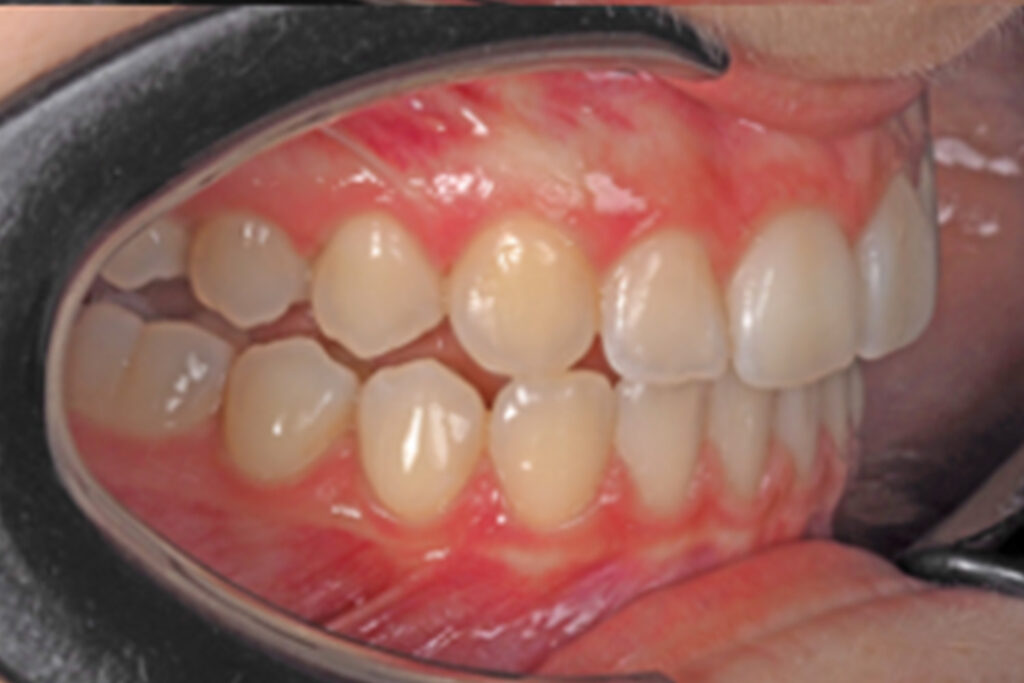

The 17-year-old female patient, who had previously undergone an orthodontic treatment 4 years ago, came to the dental clinic in May 2022. She was concerned about her upper right lateral incisor tipping, which was worsening over time, making her feel uncomfortable while smiling.

The extraoral examination revealed isometric contraction of the left side muscles, mild canted maxillary occlusal plane, facial and upper midlines centered and hypodivergent facial pattern.

During intraoral examination the patient was found to have:

Cephalometric analysis confirmed skeletal class I with meso-brachycephalic growth pattern, reducedmandibular plane, normoclined upper incisor and slightly retroclined lower incisor, increased interincisalangle and a correct occlusal plane